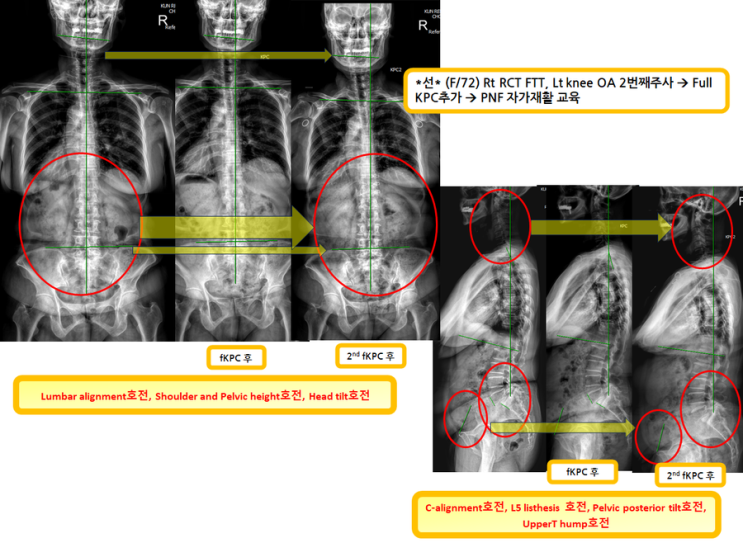

우측어깨와 좌무릎 재생주사와더불어 full KPC시행하시는 분(녹는실KPC치료는 엑스레이 호전을 10분만에 확인)

우측어깨와 좌무릎 재생주사와더불어 full KPC시행하시는 분 (녹는실KPC치료는 엑스레이 호전을 10분...